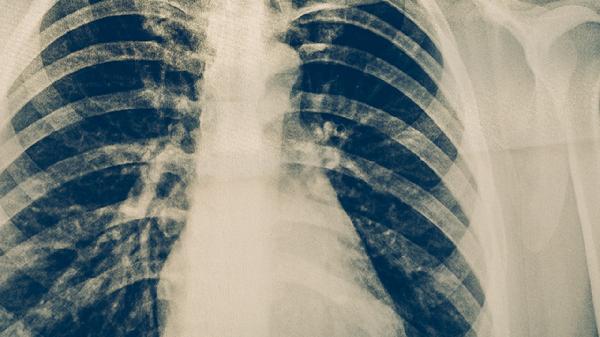

嗜酸粒细胞性支气管炎属于慢性气道炎症性疾病,典型症状为持续8周以上的干咳,夜间或晨起时加重,部分患者伴有咽喉痒感。疾病发作与嗜酸粒细胞在气道局部浸润相关,但不会像哮喘一样出现气道重塑或不可逆的肺功能损伤。通过诱导痰嗜酸粒细胞计数、肺功能检查等可明确诊断,糖皮质激素吸入治疗通常能显著缓解症状。